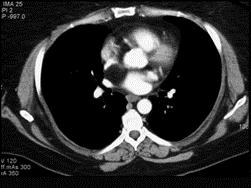

问题 女性,40岁,活动后心慌一年余,彩超发现左心房有异常回声,CT检查如图所示,应考虑为 ( )

选项 A、正常左心房 B、左心房脂肪瘤 C、左心房血栓 D、左心房脂肪浸润 E、左心房粘液瘤

答案 B